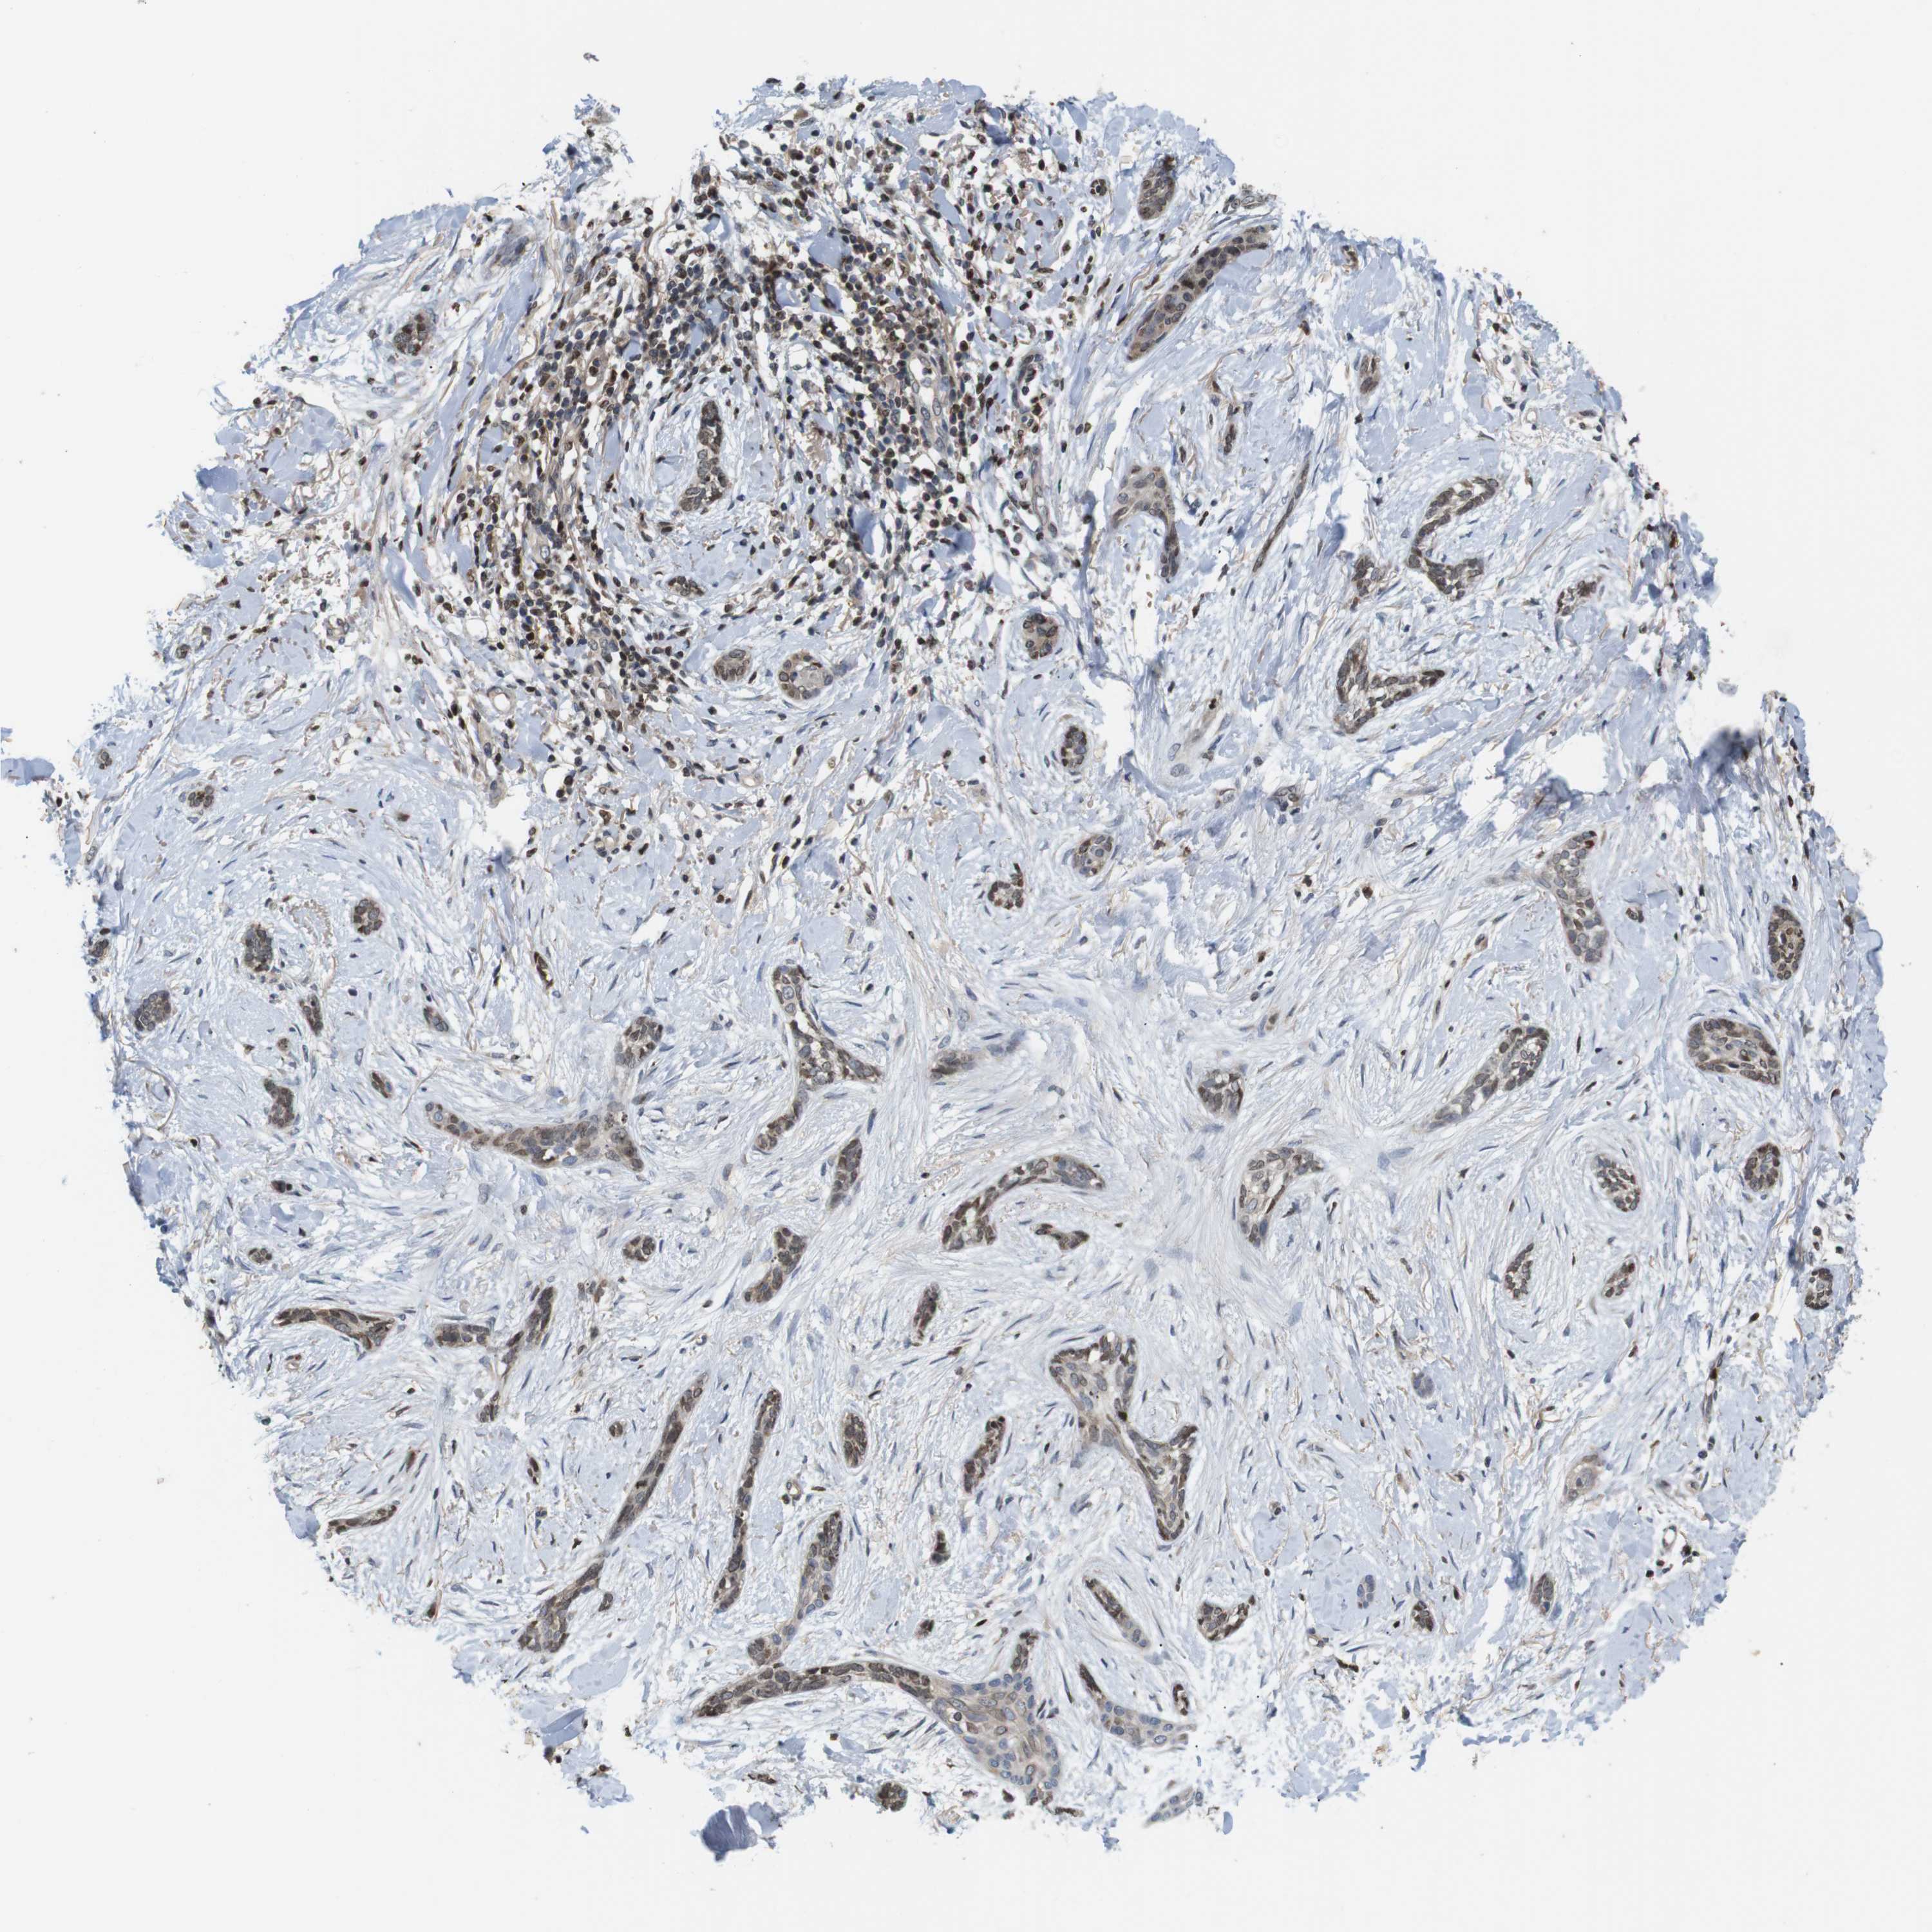

SKIN CANCER - Protein expressioni

A mouse-over function shows sample information and annotation data. Click on an image to view it in a full screen mode. Samples can be filtered based on level of antibody staining by selecting one or several of the following categories: high, medium, low and not detected. The assay and annotation is described here.

Antibody stainingi

Antibody staining in the annotated cell types in the current human tissue is reported as not detected, low, medium, or high, based on conventional immunohistochemistry profiling in selected tissues. This score is based on the combination of the staining intensity and fraction of stained cells.

Each image is clickable and will lead to virtual microscopy that enables deeper exploration of all samples and also displays staining intensity scores, fraction scores and subcellular localization as well as patient and tissue information for each sample.

Antibody CAB009017

Staining

High

Intensity

Strong

Quantity

>75%

Location

Nuclear

Squamous cell carcinoma in situ, NOS

Squamous cell carcinoma, NOS

Basal cell carcinoma

Adnexal tumor, benign

Squamous cell carcinoma, metastatic, NOS